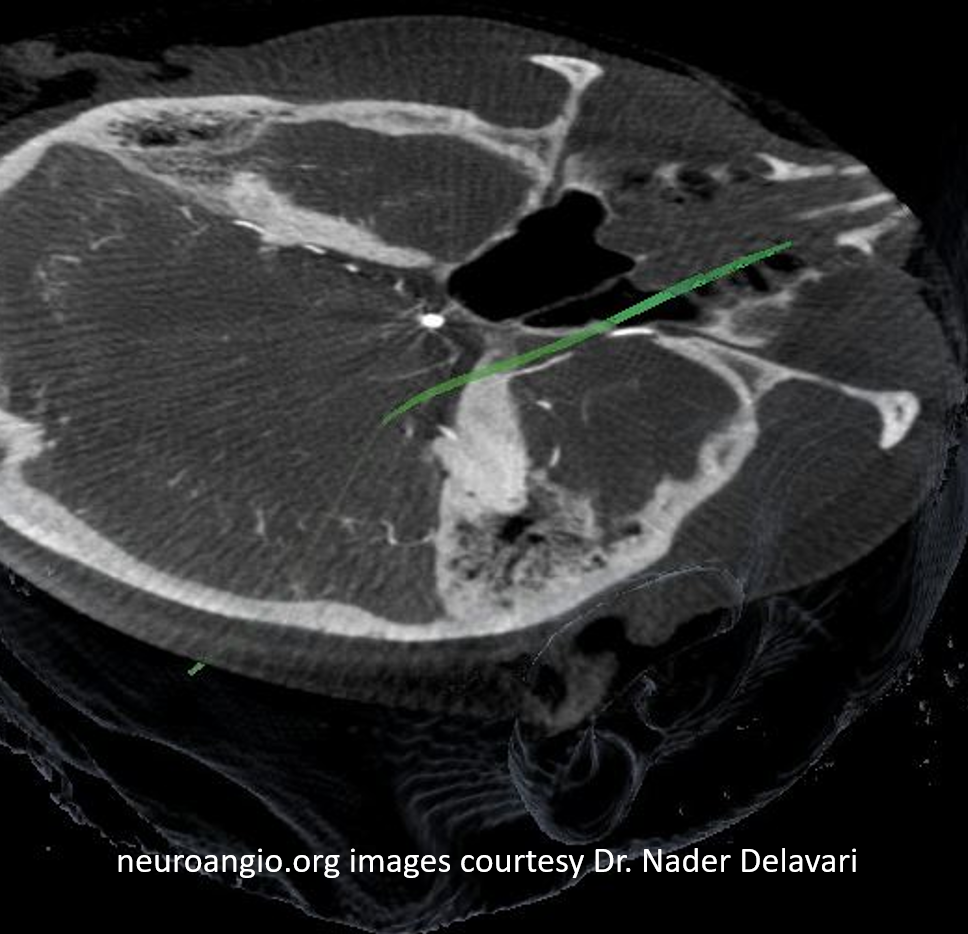

And, in case you really dont believe its the trigeminal artery, check out these co-registration images of angio (axial MIP reconstructions of rotational angio) and finally with superimposed tractography of the Vth nerve! Images courtesy Dr. Nader Delavari

Superimposed MRI and angio axials (our trigeminal artery is shown bi arrow)

Now with tractography of CN V